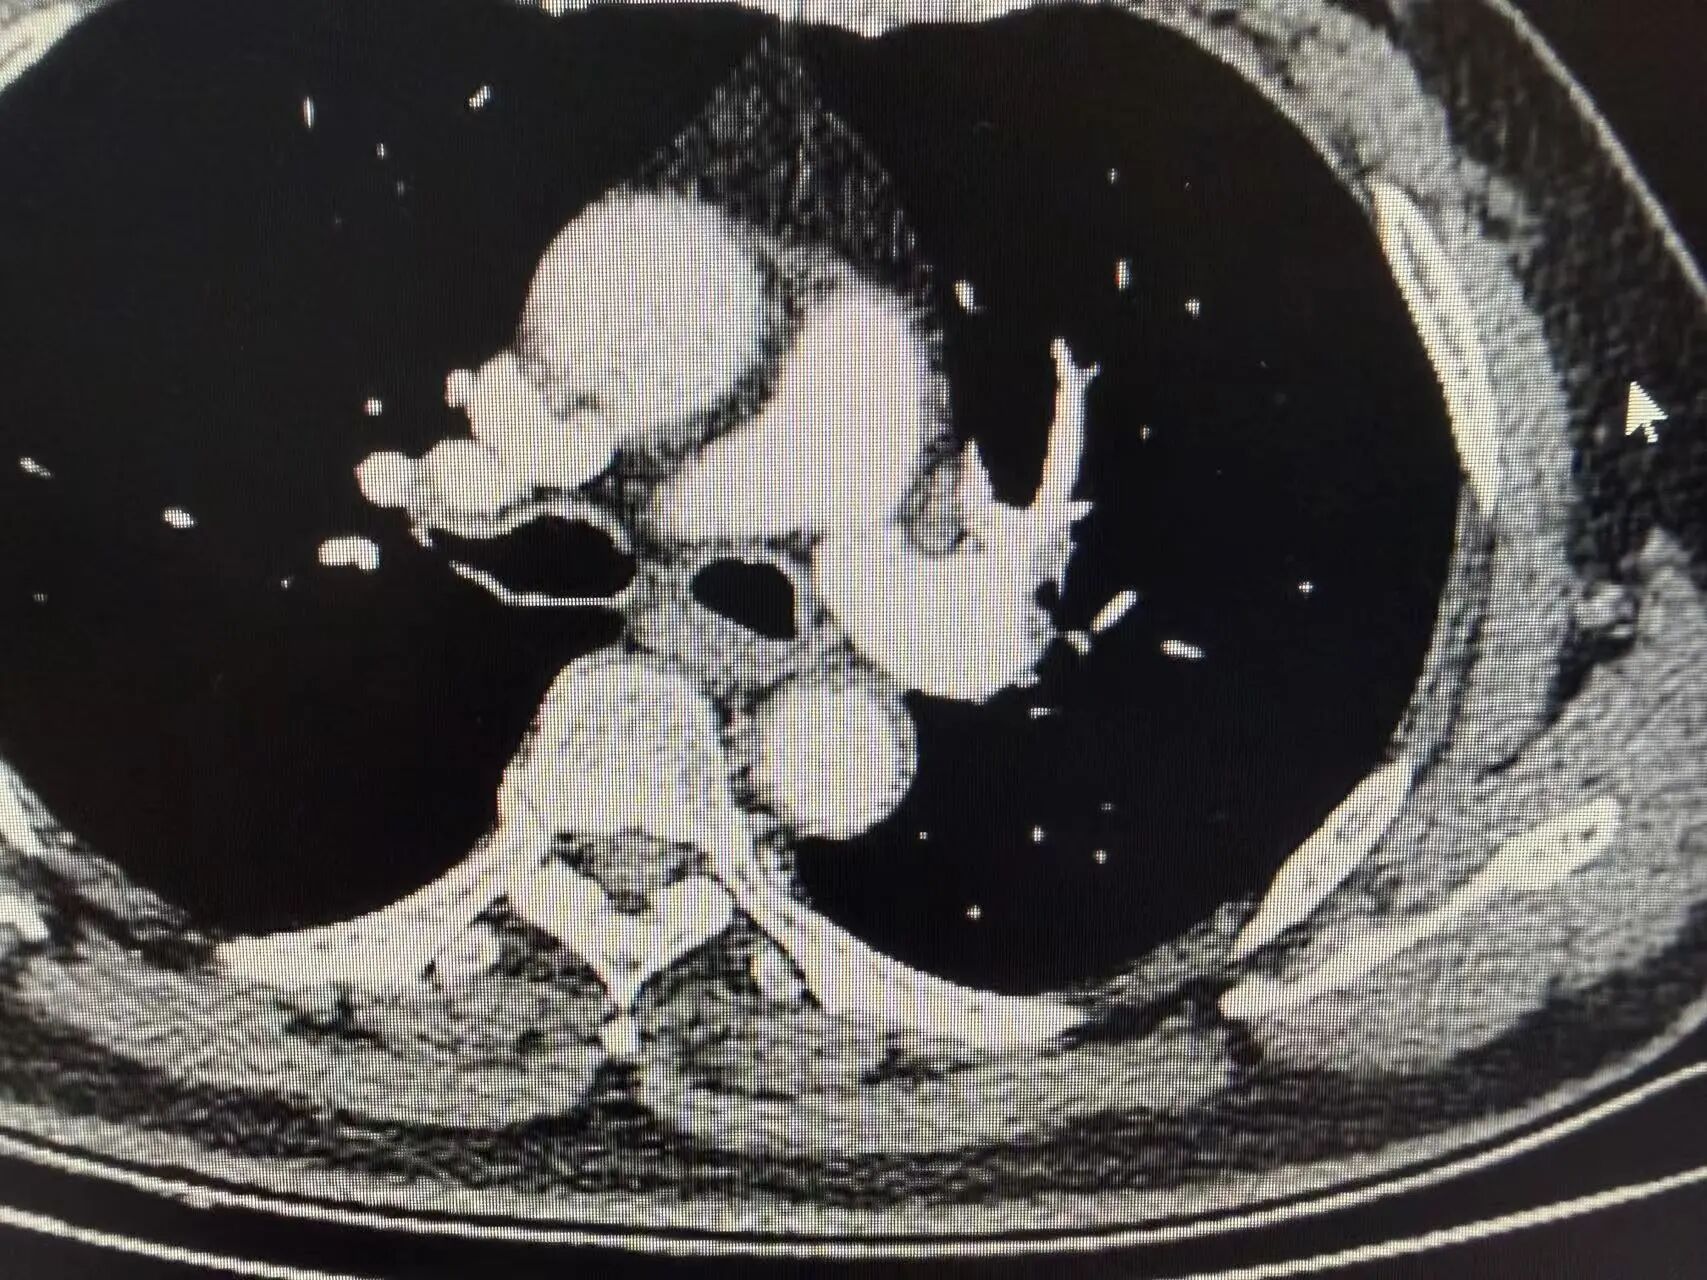

复查胸部CT显示:原左上肺肿瘤病灶显著缩小,肿大的肺门淋巴结基本恢复正常大小,肿瘤评估达到显著临床缓解,手术时机成熟

新辅助治疗后CT影像